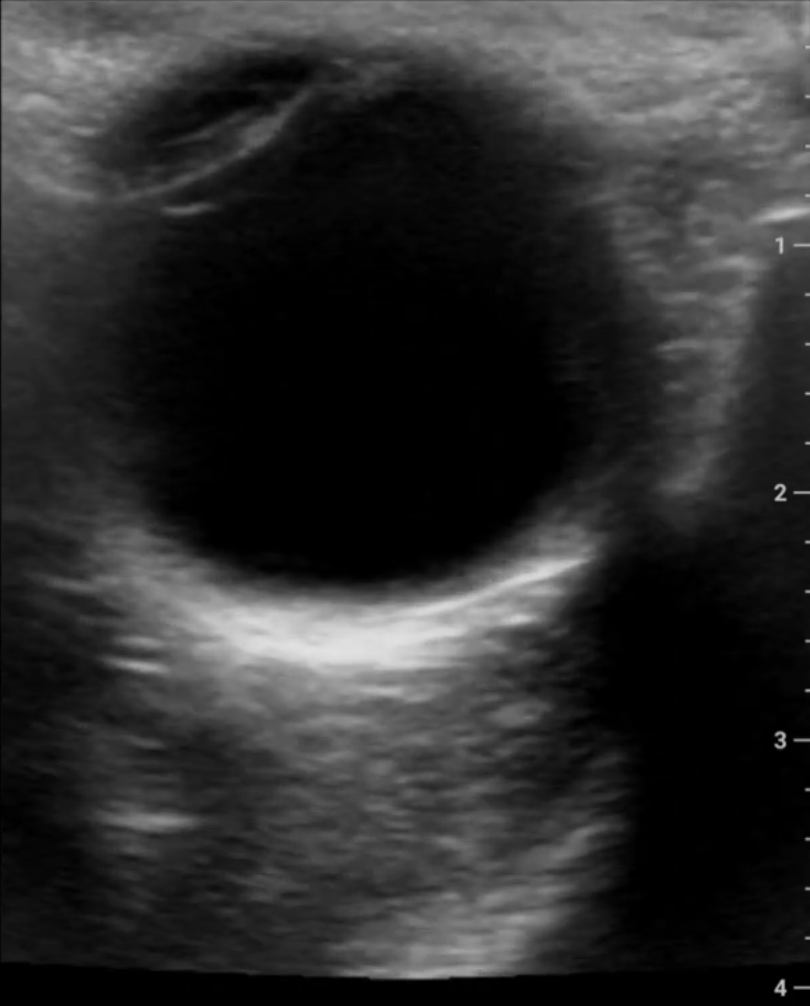

Ultrasound Images

This model of my eye was created using images captured by the device.